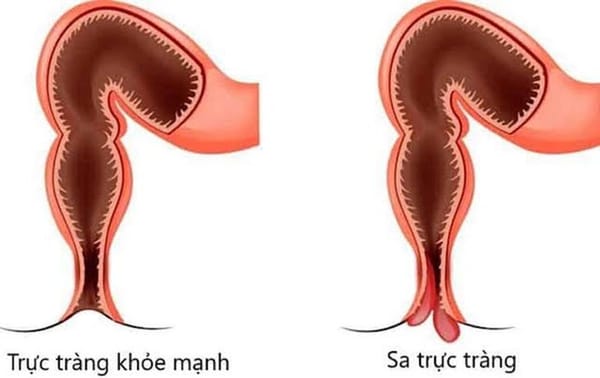

- Lao ruột: Đi tiêu lỏng hoặc đi tiêu ra đàm, máu kéo dài.